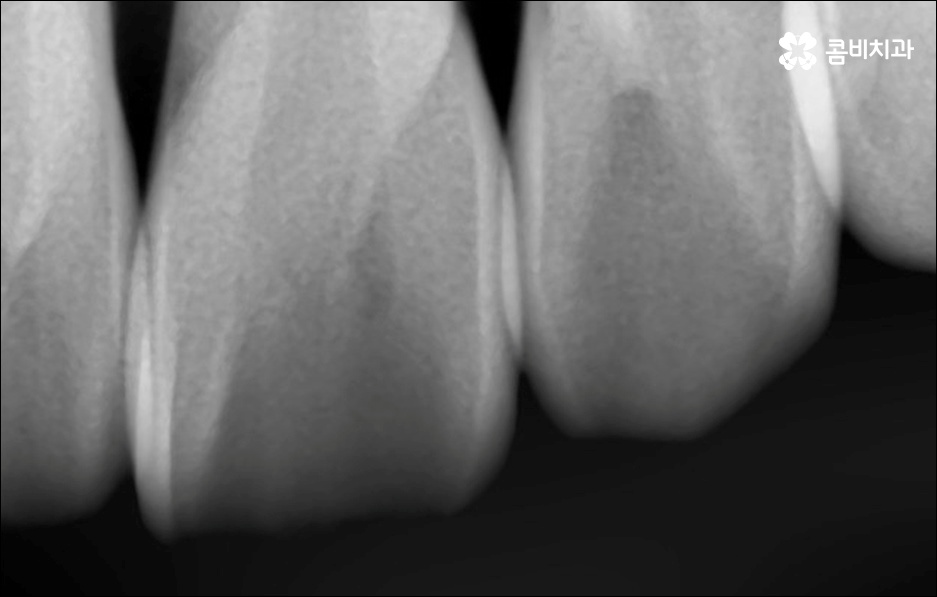

만약에 앞니 돌출 이 각도만의 문제라면 이를 교정하기 위한 치료는 좀 더 간단하게 끝날 수 있습니다. 말씀드렸던 것처럼 상황에 따라 보다 빠른 부분교정을 통해 앞니만 교정 치료를 진행할 수도 있을 거예요.

하지만 보통은 돌출된 앞니 뿐 만 아니라 골격적인 부분이 원인이 되는 경우가 많으며 이런 경우에는 상태에 맞게 전체적으로 교정을 진행하여야 교합이 올바르게 되고 입매가 전체적으로 균형감 있게 개선될 수 있어요. 이런 경우에 골격적인 원인을 무시한 채 무리하게 치아의 각도만 안쪽으로 넣으려고 하면 자칫 옥니가 될 수도 있기 때문에 이러한 부작용을 막기 위해서도 환자분들의 상황을 정확하게 검진하고 그에 맞는 교정 플랜을 세우는 것이 필요한 거예요. 물론 부정교합 정도가 심각하고 골격적인 원인이 이미 굳어진 경우와 같이 수술이 함께 필요한 케이스도 있을 수 있으나 교정 치료만으로도 튀어나온 앞니가 들어가면서 자연스럽고 부드러운 인상으로 바뀌는 경우도 많으니 먼저 검진과 상담부터 꼼꼼하게 진행해 보시길 권유드리고 있습니다. 특히 개개인의 치열, 교합, 잇몸 상태, 구강구조 등을 면밀하게 파악하고 그에 따른 정확한 치료 계획을 수립할 수 있는 경험 많은 의료진과 함께 하는 것이 중요할 수 있어요.